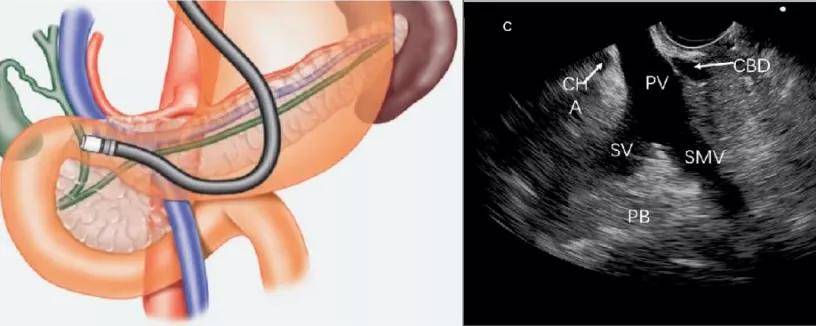

手把手教你线阵超声内镜操作及图像观察(下)

线阵超声内镜

分为小探头超声内镜(小超),环扫镜,纵轴镜(扇扫,线阵).